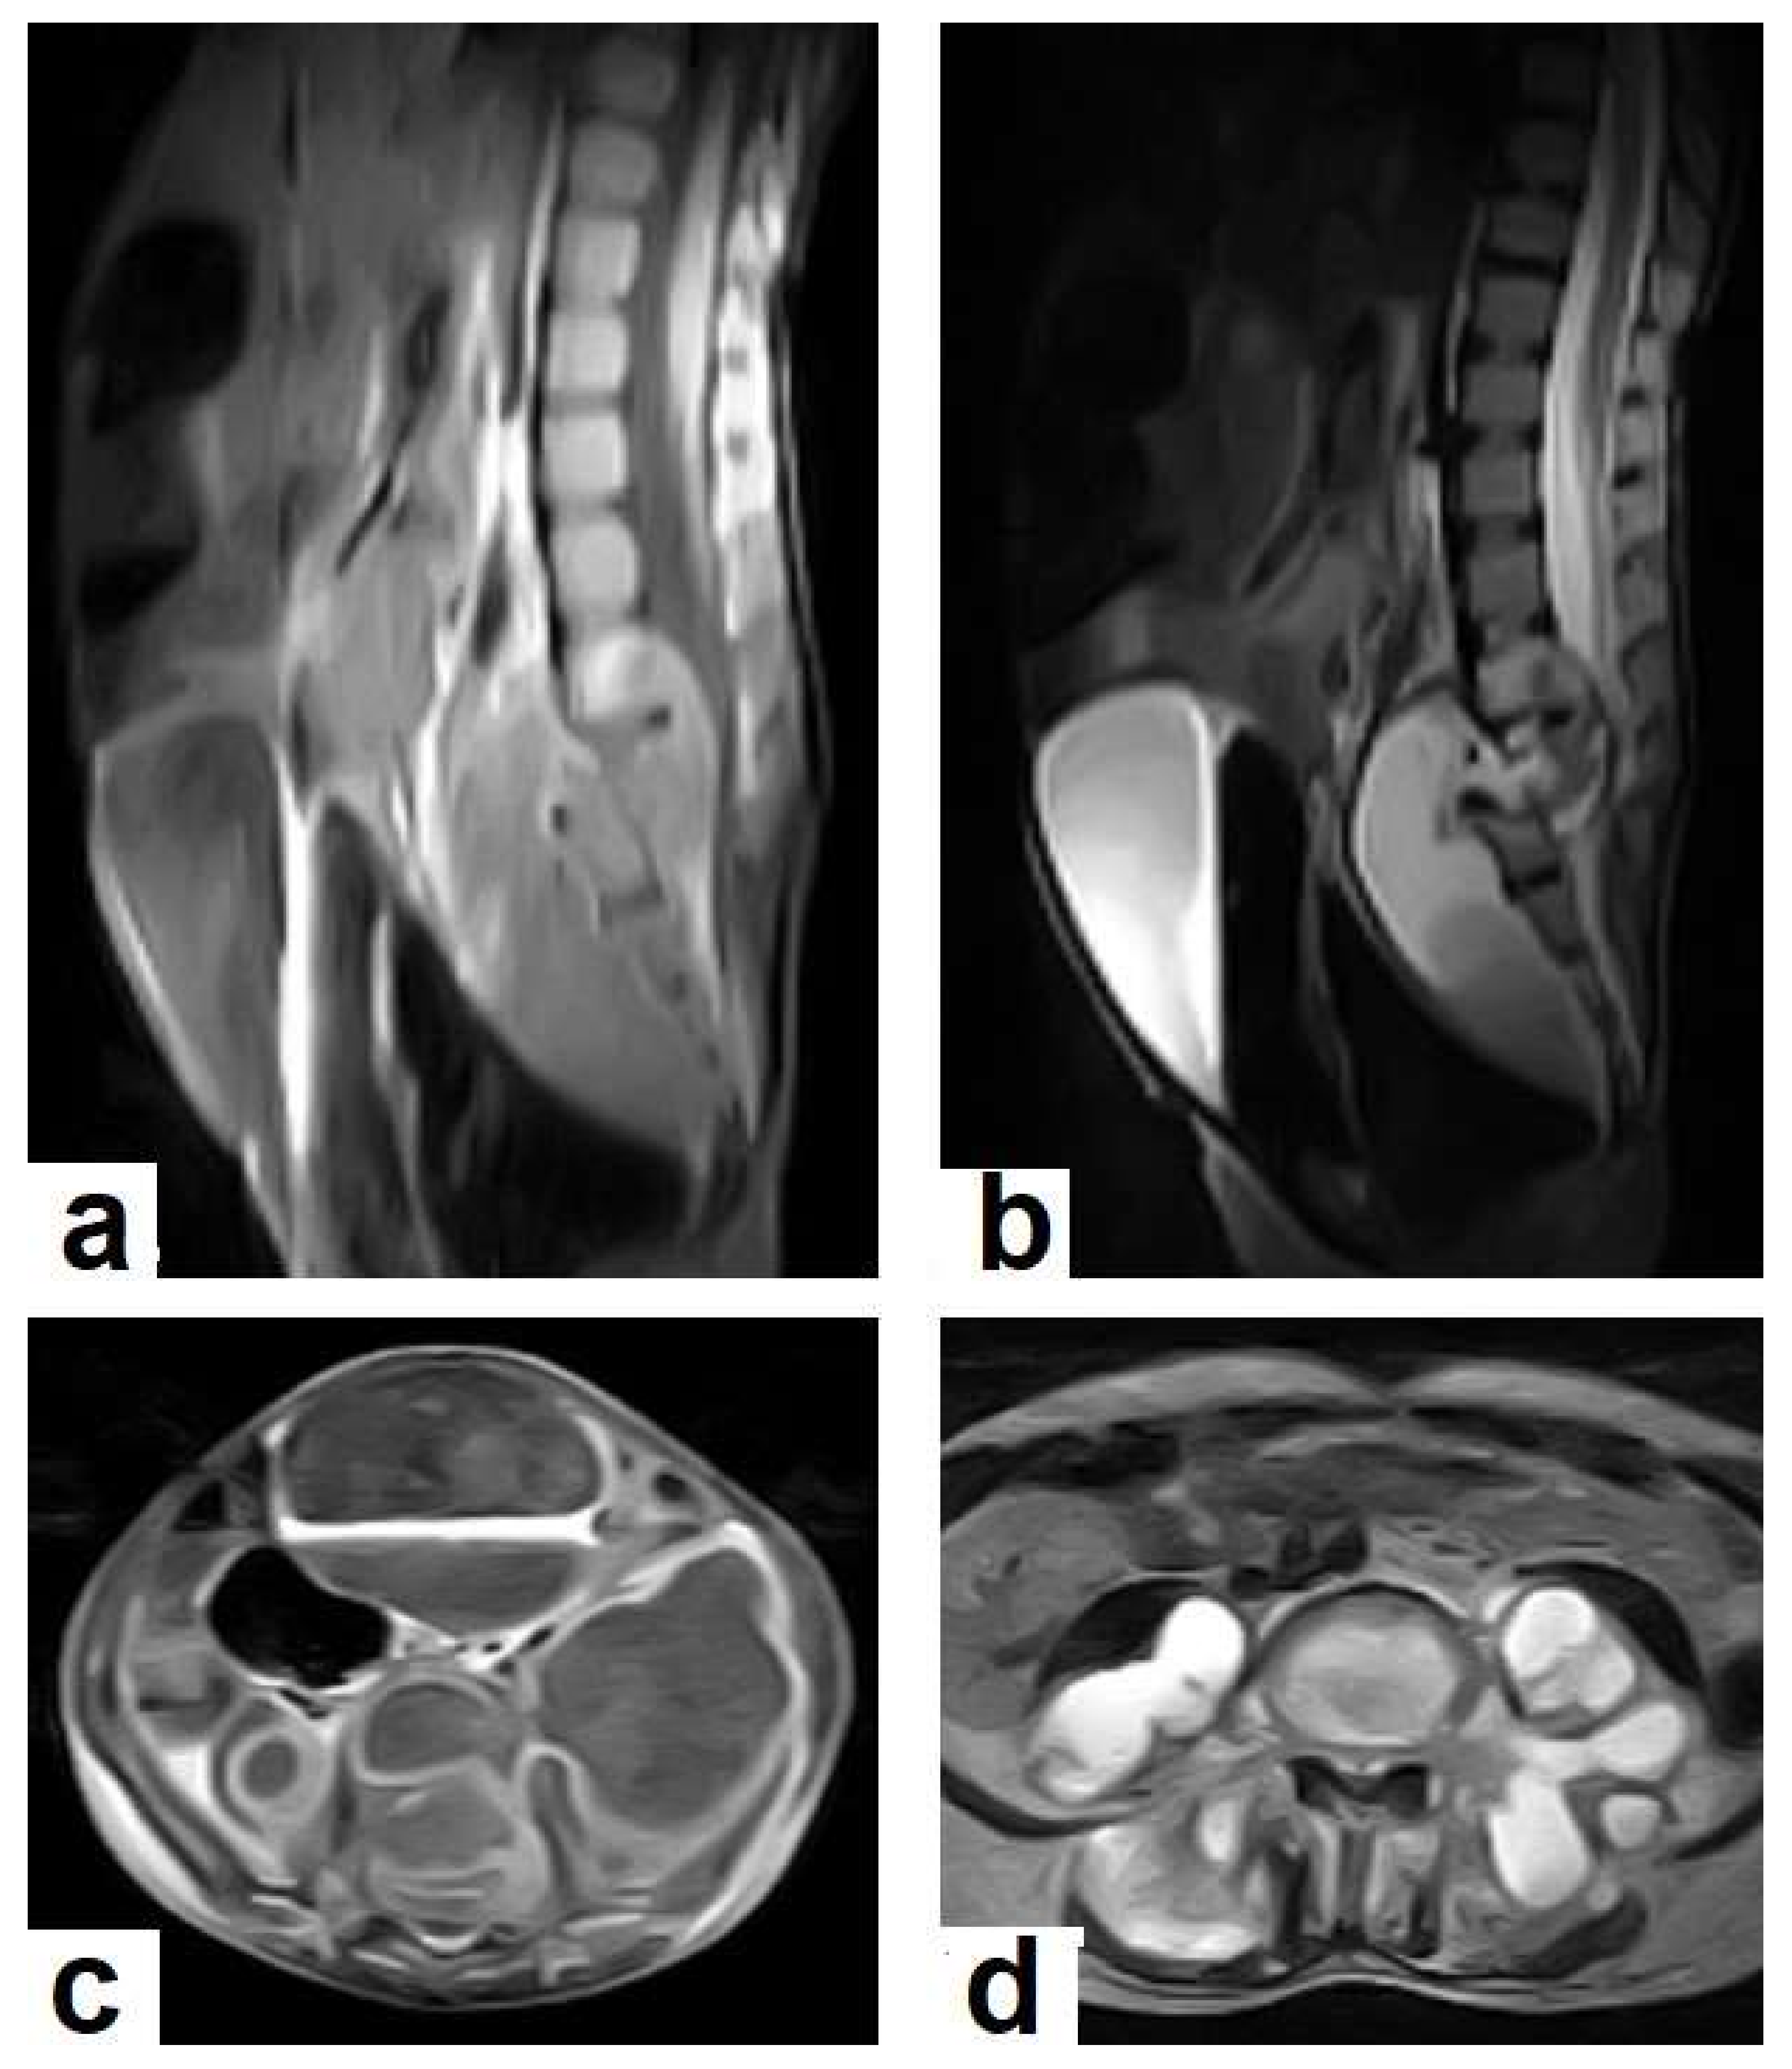

• Tuberculous spondylitis (Pott’s disease; Figure 18 and Figure 19) is a tuberculous infection of the spine that can affect any age and most commonly affects the lower thoracic and lumbar, followed by the cervical spine. It usually affects multiple contiguous vertebrae with paraspinal extension, causing subdural or epidural abscess formation and resultant spinal cord compression, which is a leading cause of paraplegia [27]. CT demonstrates the extent of bone involvement, while MRI demonstrates spinal-cord and soft-tissue involvement. Tuberculous spondylitis appears as a well-defined paraspinal abnormal signal intensity, as a thin wall abscess, or a combination of intraosseous and soft tissue abscesses. The spread of infection is sub-ligamentous beneath the anterior longitudinal ligament involving multiple vertebrae with high signal intensity on T2WIs. Pott’s disease is a difficult differential diagnosis with a spinal pyogenic infection. MRI demonstrate have 100% sensitivity, 80% specificity, and 90% accuracy in differentiating tuberculous from pyogenic spinal infection [34].

2.7. Musculoskeletal (MSK) TB

TB can affect any part of the musculoskeletal (MSK) system, and symptoms of TB may be insidious, causing TB not to be considered. CT and MRI imaging modalities can bring suspicion to TB diagnoses [57]. MSK TB has a wide range of radiological features that can mimic many pathologies all over the body. However, radiological assessment is often the first step in the diagnosis of MSK TB [58]. The most common type of MSK TB is tuberculous spondylodiscitis (Potts disease), which accounts for 50% of MSK TB [57,58] (Figure 18 and Figure 19). Osteoarthritis TB affects joints or bones. It usually affects long weight-bearing bones and sometimes affects the ribs. Articular TB usually presents as monoarthritis in the knee (Figure 24) or the hip joints. However, sacroiliac, and sternoclavicular joints are also sometimes affected. The predilection of TB to affect the vertebrae and the large joints is due to the rich blood supply to the vertebrae and the growth plates of the long bones [59]. TB arthritis presents as a slow progressive destructive monoarthritis, so the diagnosis is delayed due to the indolent onset and low clinical suspicion [60].

On medical imaging, TB may initially show soft tissue swelling and later progress to periosteal thickening, osteopenia, periarticular bone destruction, and cold abscesses, and fistulae may develop in late cases. MSK TB is a differential diagnosis of a wide bone lesion. At the early stages, it is often misdiagnosed as traumatic lesions, degenerative joint disease, gout, pseudo gout, rheumatoid arthritis, or pigmented villonodular synovitis. High suspicion of TB is required, and a final diagnosis can be carried out by using arthrocentesis and a mycobacterial culture; in addition, a synovial biopsy is often needed [59,60].

Figure 19. Pott’s disease in a 6-year-old female patient. Selected images of lumbosacral MRI. Sagittal (a) T1-weighted images and (b) T2-weighted images show that destructive lesion involves the T4/T5 disc and vertebrae, with extensive pre-vertebral loculated fluid collection. Selected axial images of MRI (c) T1-weighted image with gadolinium, and (d) T2-weighted image shows bilateral paravertebral loculated fluid collections involved in bilateral psoas; paravertebral muscles appear to have low-signal-intensity contents on T1-WIs with marginal enhancement after contrast administration and high-signal-intensity contents on T2-WIs (arrows). The picture is typical of Pott’s disease with bilateral psoas and paravertebral abscesses.